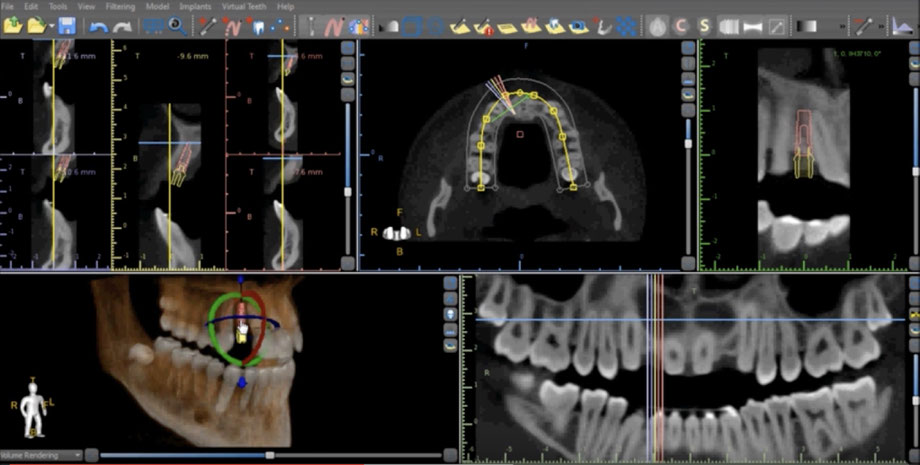

Pour des cas complexes, nous utilisons la préparation virtuelle via les outils informatiques. Dans ce but nous réalisons un scanner (de préférence CTCB) des mâchoires et dans les cas complexes, une empreinte optique de la bouche. Cela nous permet d'étudier non seulement l'emplacement des dents prothétiques mais aussi de placer les implants dentaires de la manière la plus adéquate dans l'os disponible, c'est-à-dire en utilisant au mieux les volumes osseux tout en évitant les zones dangereuses. Le placement des implants est donc d'abord réalisé de façon virtuelle sur l'ordinateur. Quand nous sommes satisfaits du résultat un guide chirurgical est confectionné à l'aide d'une imprimante 3D pour les cas complexes.

Cela nous permet alors de placer les implants de façon très précise et de manière quasiment atraumatique grâce au guide  chirurgical.